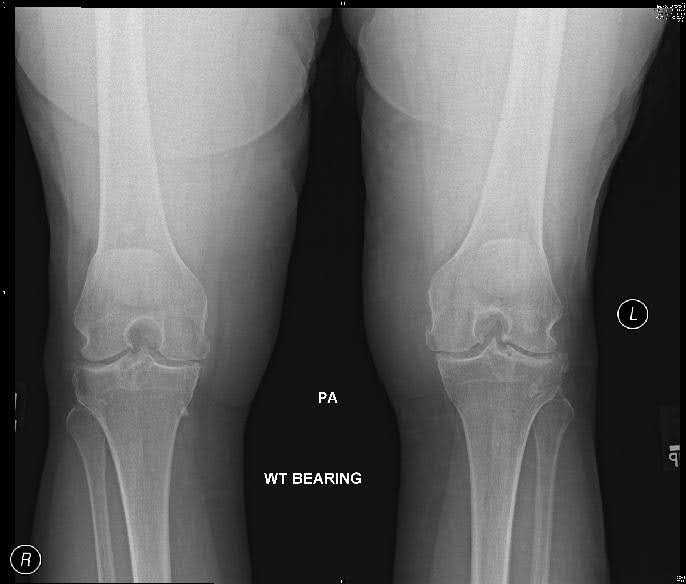

Imaging

AP weight-bearing views including bilateral knees, lateral, and sunrise views are necessary to assess knee osteoarthritis radiographically. The critical findings of knee osteoarthritis on radiologic exam are as follows:2

- Joint space narrowing

- Osteophytes

- Subchondral sclerosis

- Subchondral cysts

- Loss of bone stock

- Malalignment

- Varus or valgus deformity

Finding osteophytes on x-ray best differentiates osteoarthritis from rheumatoid and other arthritides. A sensitive and specific criteria for knee osteoarthritis is the combination of knee pain, radiologic appearance of osteophytes and one or more of the following: age over 50 years, morning stiffness less than 30 minutes, or crepitus on active motion.

Bilateral weight-bearing views should be used to compare the affected with the unaffected side. Osteoarthritis should be assessed in each of the three knee compartments: medial, lateral, and patellofemoral. It should be noted that as many as 30% of adults over 65 years will demonstrate radiographic appearance of osteoarthritis, but one-third of these individuals will be asymptomatic.3 Thus, it is important to correlate clinical and radiographic findings to reach a diagnosis of symptomatic knee osteoarthritis, a clinically relevant entity.

Pre-op X-Rays

Figure 1. Pre-op x-rays.